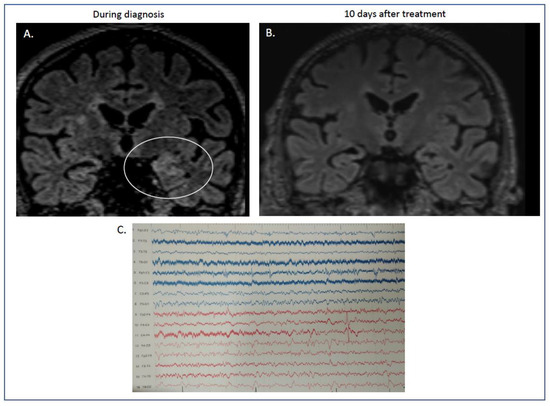

| indirect immunofluorescence on unfixed murine brain sections | CSF | positive (granular layer of cerebellum, neuronal cells of hippocampus) | |